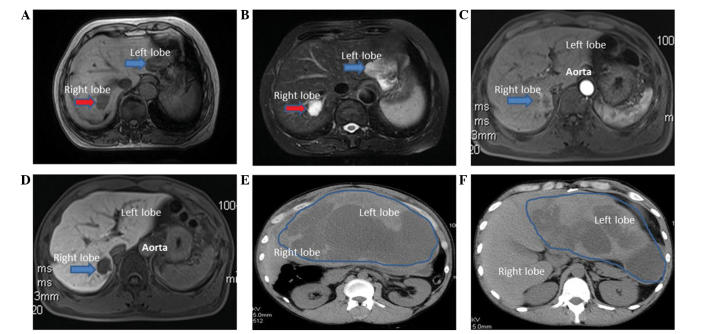

A 60-year-old woman was admitted to the China-Japan Union Hospital of Jilin University on August 22, 2014, due to the presence of liver masses, which were noted during routine physical examination. The medical history of the patient was significant for type B hepatitis. The levels of serum alpha-fetoprotein (AFP) were normal (3.0 µg/l; normal range, 0–20 µg/l). Abdominal magnetic resonance imaging (MRI; MAGNETOM Avanto 1.5; Siemens AG, Munich, Germany) revealed two hepatic masses. The mass in the right lobe was hypointense on T1-weighted images and hyperintense on T2-weighted images, which were typical features of hepatic hemangioma (3). The other mass was located in the left lobe, and was unequally isointense on T1-weighted images and mildly hyperintense on T2-weighted images (Fig. 1), thus being difficult to differentiate from hepatoma. A laparoscopic hepatic left lateral lobectomy was performed, and a neoplasia of 4 cm in diameter, which was protruding from the liver surface, was identified. Post-surgical pathology concluded that the tumor was a hepatic EAML. For immunohistochemistry, specimens were incubated overnight at 4°C with the following antibodies: Monoclonal mouse anti-human HMB-45 (#ab787; Abcam, Cambridge, UK), monoclonal mouse anti-human melan A (#sc-271432; Santa Cruz Biotechnology, Inc., Dallas, TX, USA), monoclonal rabbit anti-S-100 (#ab52642; Abcam), monoclonal rabbit anti-vimentin (VIM; #ab92547; Abcam), monoclonal mouse anti-human cluster of differentiation (CD)34 (#sc-19587; Santa Cruz Biotechnology, Inc.), monoclonal mouse anti-pan-cytokeratin (CK; #ab6401; Abcam), monoclonal mouse anti-human hepatocyte (#ab75677; Abcam), polyclonal rabbit anti-α smooth muscle actin (SMA; #ab5694; Abcam) and monoclonal rabbit anti-glypican-3 (#ab124829; Abcam). All antibodies were diluted to a dilution ratio of 1:500 with 1% bovine serum albumin, 0.05% sodium azide and 0.01 M phosphate-buffered saline (pH 7.2). Staining demonstrated the tumor to be positive for HMB-45, melan A, S-100, SMA, VIM and CD34, but negative for CK, hepatocyte and glypican-3 (GPC-3). Ki-67+ cells accounted for 1%.

Figure 1.

(A and B) MRI conducted on a 60-year-old woman with hepatic hemangioma and hepatic EAML revealed two tumors. The right lobe tumor was hypointense on T1-weighted images (A; red arrow) and hyperintense on T2-weighted images (B; red arrow), which are the typical imaging manifestations of hepatic hemangioma. The left lobe tumor displayed an unequal isointense pattern on T1-weighted images (A; blue arrow) and a mildly hyperintense signal in T2-weighted images (B; blue arrow). (C and D) MRI performed on a 46-year-old man with hepatic EAML in the right posterior lobe revealed tumor ring-enhancements in the arterial phase (C; blue arrow), with a decrease in the portal venous/delayed phase (D; blue arrow). (E and F) A CT scan performed on a 37-year-old man with a giant hepatic EAML in the left lateral lobe revealed a well-defined cystic mass located in the left lobe of the liver. These images show different scanning planes of the CT scan. The blue line circled the location of the tumor. MRI, magnetic resonance imaging; EAML, epithelioid angiomyolipoma; CT, computed tomography.

A 46-year-old man was admitted to hospital on August 30, 2013, due to a mass in the right hepatic lobe, which was noticed during routine physical examination. Viral hepatitis serology was negative and serum AFP levels were normal (5.7 µg/l; normal range, 0–20 µg/l). MRI revealed a 2.8-cm mass in the right posterior lobe, which was hypointense on T1-weighted images and hyperintense on T2-weighted images. The tumor exhibited ring-enhancements in the arterial phase, with a decrease in the portal venous/delayed phase (Fig. 1). The pathology results of an ultrasound (iU22 xMATRIX; Philips Healthcare, Andover, MA, USA)-guided fine-needle aspiration biopsy (FNAB) revealed hyperplastic lesions of pleomorphic cells. The neoplasia was removed by surgical resection. Post-surgical pathology confirmed the diagnosis of hepatic EAML. For immunohistochemistry, specimens were incubated overnight at 4°C with the following antibodies: Monoclonal mouse anti-human HMB-45, monoclonal mouse anti-human melan A, monoclonal mouse anti-human CD34, monoclonal rabbit anti-VIM, monoclonal rabbit anti-S-100, polyclonal rabbit anti-epithelial membrane antigen (EMA; #P15941; Abgent, Inc., San Diego, CA, USA), monoclonal mouse anti-pan-CK and monoclonal mouse anti-human hepatocyte. All antibodies were diluted with 1% bovine serum albumin, 0.05% sodium azide and 0.01 M phosphate-buffered saline (pH, 7.2). Tumor cells were positive for HMB-45, melan A, SMA, CD34 and VIM, but negative for S-100, EMA, CK and hepatocyte. Ki-67+ cells accounted for <1%.

A 37-year-old man presented to the emergency room on September 26, 2014, complaining of persistent abdominal pain, nausea and vomiting. Serum carbohydrate antigen 19–9 levels were elevated (168.55 U/ml; normal range, 0.00–37.00 U/ml). Abdominal contrast-enhanced computed tomography (CT; Discovery CT750 HD; GE Healthcare Bio-Sciences, Pittsburgh, PA, USA) revealed a giant hepatic tumor in the left lateral lobe. The tumor was 15.6×6.3×28.9 cm in size, and contained cystic and solid components (Fig. 1). The margins and septa of the tumor were enhanced in the arterial phase and decreased in the portal venous/delayed phase. The surgically resected specimen contained a ruptured tumor with an outflow of kermesinus fluid from the ruptured area (Fig. 2). The net weight of the tumor was 10 kg and its diameter was 32.0 cm. Pathology confirmed the diagnosis of hepatic EAML. Part of the tumor tissue was necrotic. For immunohistochemistry, specimens were incubated overnight at 4°C with the following antibodies: Monoclonal mouse anti-human HMB-45, monoclonal mouse anti-human melan A, monoclonal mouse anti-human CD34, monoclonal rabbit anti-S-100, polyclonal rabbit anti-EMA (#P15941; Abgent, Inc., San Diego, CA, USA), polyclonal rabbit anti-human AFP (#ab182645; Abcam), monoclonal mouse anti-pan-CK, monoclonal mouse anti-human hepatocyte, polyclonal rabbit anti-chromogranin (#P10645; Abgent, Inc.) and polyclonal rabbit anti-synaptophysin (#ab14692; Abcam). All antibodies were diluted with 1% bovine serum albumin, 0.05% sodium azide and 0.01 M phosphate-buffered saline (pH, 7.2). All antibodies were diluted with 1% bovine serum albumin. 0.05% sodium azide and 0.01 M phosphate-buffered saline (pH, 7.2). Staining was positive for HMB-45, melan A, SMA and CD34, but negative for S-100, EMA, AFP, CK, hepatocyte, GPC-3, chromogranin and synaptophysin (Fig. 3). Ki-67+ cells accounted for 2%.

Imaging features of hepatic EAML vary from case to case and may lack specificity (24). Usually, the imaging features of the tumors are associated with histological components (24). Thus, the majority of reported hepatic EAML tumors were completely devoid of adipose tissue, and fat attenuation was rarely observed in CT or MRI images (24). By contrast, nearly all tumors were markedly enhanced in the arterial phase, indicating that hepatic EAML is a hypervascularized tumor (7). There are two types of enhancement patterns in the portal venous/delayed phase (25): Lesions with abundant central vessels exhibited a rapid contrast decrease, whereas lesions with small or no vessels demonstrated prolonged enhancement (26). The majority of lesions exhibited a significantly reduced contrast in the portal venous/delayed phase (24). Accordingly, the tumor in case 2 revealed ring-enhancements in the arterial phase with a decrease in the portal venous/delayed phase, while the margins and septa of the tumor in case 3 were enhanced in the arterial phase and decreased in the portal venous/delayed phase.